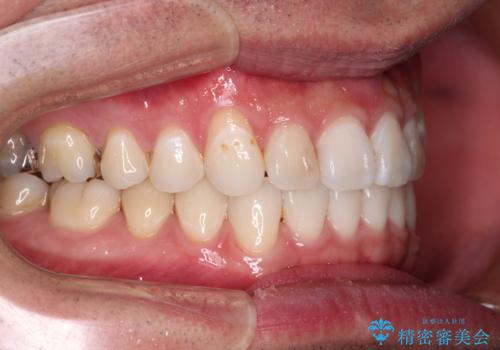

- 上下前歯の叢生を気にして来院された患者様です。

費用を抑え、期間もあまりかけずに治療をしたいとのことで、インビザライン・ライトを用いて矯正治療を行うこととしました。